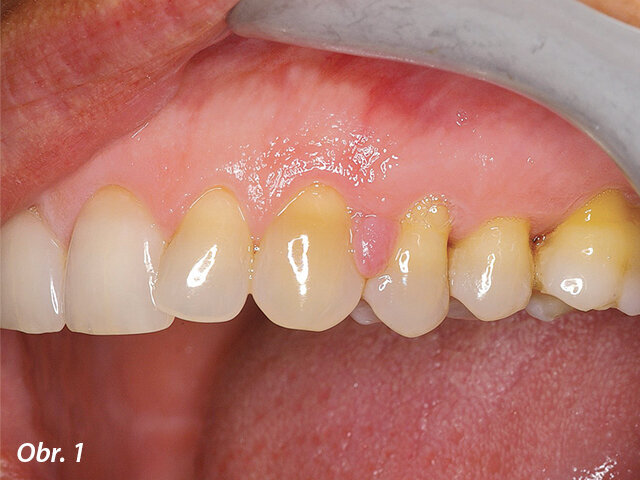

Jak je patrno z obrázku 1, pacientka se dostavila do mé ordinace s lokalizovanou hutnou hyperplastickou oblastí dásně, která byla potvrzena klinickým vyšetřením. 31letá pacientka měla elegantní oblečení a čisté, dobře udržované ruce a nehty. Stěžovala si, jak je těžké danou lokalizovanou oblast čistit a popisovala, že snaha o vyčištění bolí a způsobuje krvácení, především při použití dentální nitě. Došlo k narušení kontinuity hladkého vzhledu gingivy, díky čemuž vypadal její povrch nerovně a esteticky rušivě.

Hutná hyperplastická tkáň interproximálně mezi zuby 23 a 24. Hyperplasticky změněná tkáň omezovala přístup do interdentálního prostoru, v důsledku čehož nebyla pacientka schopna provádět v inkriminované oblasti řádnou ústní hygienu.